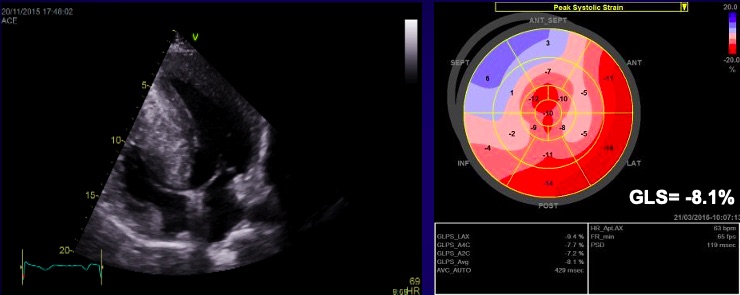

The causes of RCM can be classified as non-infiltrative (familial) or infiltrative (storage diseases), but the same pattern can be found in other disorders like diabetic cardiomyopathy, scleroderma, and endomyocardial fibrosis [38, 39, 40]. An accurate myocardial investigation by MRI and myocardial scintigraphy allows the diagnosis of different types of myocardial amyloidosis which is increasingly observed in the elderly either by transthyretin (aTTR) or by AL–light immunoglobulin chains in different plasmacytomas [41]. Another type of RCM is found in sarcoidosis and it can cause global or regional LV wall motion abnormalities. In some cases, the changes are specifically revealed on the basal posterior and lateral wall of the LV [42, 43, 44]. The most common finding is myocardial thinning, but RCM can also present with hypertrophy or it can include myocardial aneurysms [38, 45, 46, 47]. In some RCMs such as endomyocardial fibrosis or hypereosinophilic syndrome apical intraventricular thrombosis may be recognized; this may be responsible for pulmonary or systemic cardioembolism [48]. In RCM due to amyloidosis, apart from hypertrophy and wall motion abnormalities (Fig. 9), valvular involvement may also be noted with thickened aortic cusps or mitral leaflets determined by local deposition of amyloid [49].

Fig. 9.The echocardiographic aspect of cardiac amyloidosis, associated with aortic stenosis. (A) short-axis view, showing left ventricular hypertrophy. (B) Speckle tracking echocardiography obtained by measuring longitudinal strain in apical 4 chamber view, shows a significantly reduced GLS (global longitudinal strain) of –8.6%.